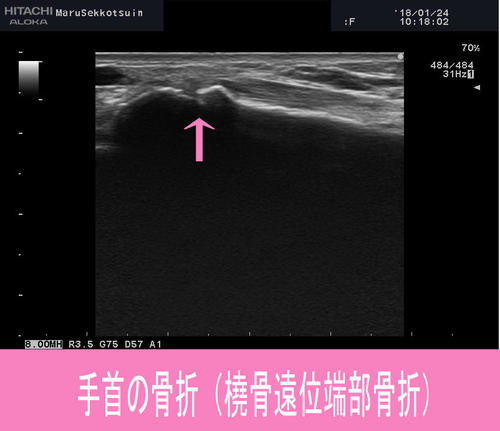

その中のお一人、しっかり問診、触診、そしてエコー検査。

やはり発生機序、腫れ方から、手首の橈骨という骨の骨折と判明。

「橈骨遠位端部骨折」という骨折です。